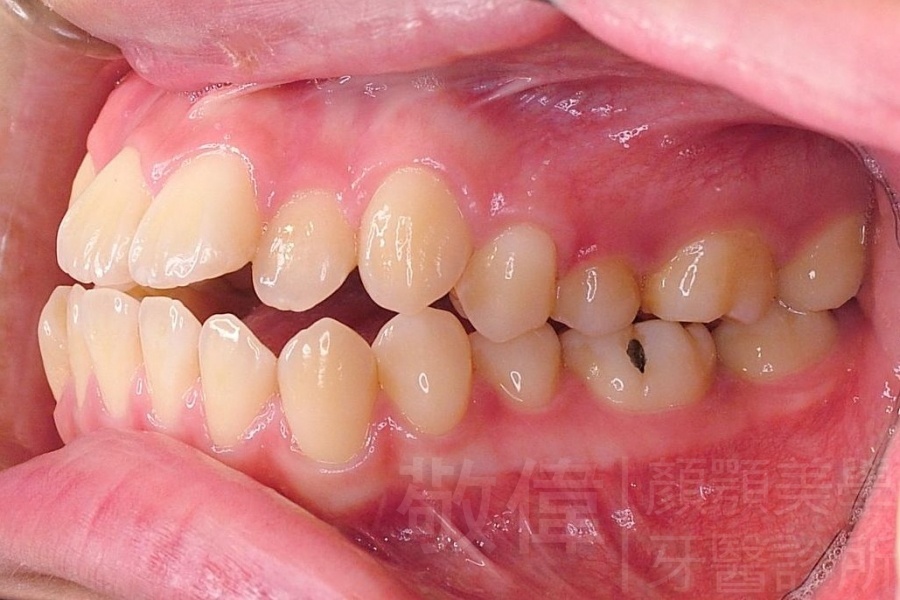

齒顏矯正/戽斗、亂牙、爛牙,變身 免植牙的健牙美女

<個案說明>

變臉矯正,原來戽斗妹跟大歪臉變成自信正妹

經由本院3D數影X光影像儀分析、與3D齒顎顏矯正技術,再配合口腔顎面正顎專科醫師施以正顎手術治療,雙方共同合作,使患者臉部外觀有很好的改善,大歪變小歪,產生了天南地北的大改變,她的人生也整個變得不一樣。

因為矯正與正顎手術的配合,使「戽斗妹」變成了「陽光正妹」,完全的改變了她的人生,在面對各種場合、與人交際都散發出自信微笑。所以,奉勸家長,如果小朋友有臉顎畸型的問題,應該考慮配合做這種簡單、安全、有效的正顎手術。